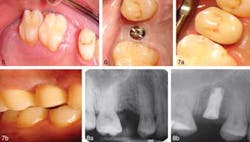

Patient 2.Figure 5. Patient 1. Occlusal view prior to the procedure. Figure 6. Occlusal view of the healing abutment in place one week after implant insertion. Figure 7. Occlusal and lateral postoperative view of the prosthesis in place. Figure 8. Digital periapical radiograph view before implant placement one week after implant insertion with healing abutment in place. The authors of this study propose designating this technique the “WarLess procedure” — incorporating “warfarin” and “flapless.” This preliminary study shows that flapless dental implant surgery can be safe and effective for patients without interruption of anticoagulant medication. Larger clinical trials are needed to confirm the safety of the technique on a broader scale. Full text of the article, “Flapless Dental Implant Surgery for Patients on Oral Anticoagulants — The ‘WarLess Procedure’: A Report of 2 Cases,” Journal of Oral Implantology, Vol. 39, Special Issue, 2013, is available here.About Journal of Oral Implantology The Journal of Oral Implantology is the official publication of the American Academy of Implant Dentistry and of the American Academy of Implant Prosthodontics. It is dedicated to providing valuable information to general dentists, oral surgeons, prosthodontists, periodontists, scientists, clinicians, laboratory owners and technicians, manufacturers, and educators. The JOI distinguishes itself as the first and oldest journal in the world devoted exclusively to implant dentistry. For more information about the journal or society, please visit their website.